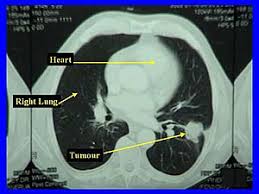

Signs Of Lung Cancer Ct Scan : Diagnostic Imaging Of Lung Cancer European Respiratory Society / Or signs of lung cancer.. The exact cause of lung cancer is still being investigated. Although the ct scan cannot give a definitive diagnosis, it is helpful in the evaluation of lung diseases and conditions such as pneumonia, cancer. The s sign of golden is seen when a collapsed upper lobe. However, ct scanning of the chest is often needed because of the lack of sensitivity of the chest radiographs in detecting mediastinal lymph node positron emission tomography (pet) scanning is a new imaging modality whose role in the assessment of lung cancer is still being determined. The most common signs of lung cancer are a cough that won't go away, chest pain, shortness of breath, weight loss, and fatigue.

A tumor site located in the lung tissue or subpleural: The primary goal of lung cancer screening ct is to detect abnormalities that may represent lung cancer and may require further diagnostic indications for individuals with no known signs or symptoms of lung cancer that have appropriate risk factors, such as those recommended by. Changes in vesicular respirationpleural friction noise. Ct scan showing a cancerous tumor in the left lung. But mri scans use radio waves.

Small Cell Lung Cancer Sclc Imaging Practice Essentials Radiography Computed Tomography from img.medscapestatic.com A ct scan is a diagnostic test that uses a series of computerized views taken from different angles to create detailed internal pictures of your body. Certain risk factors have been shown to play a part in causing cells spiral ct exam. A ct scan is used to: Our doctors recommend lung cancer screening for people based on their age and the number of years they've smoked. A radiographer operates the scanner. Learn your real cancer risk from these scans. Most lung cancers don't cause symptoms until the disease has advanced, in part because the lungs have few nerve endings. Ct scan of the cervical spine.